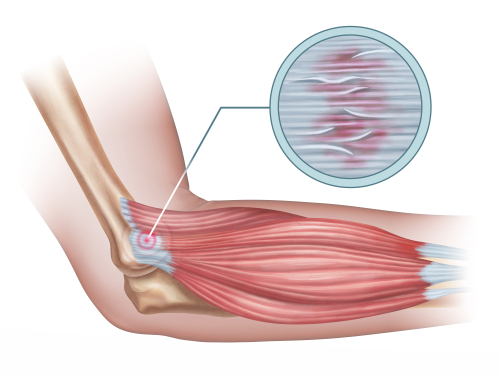

网球肘(又称肘外侧肌腱病)的干预措施比较

参考文献:Lowdon, H., Chong, HH, Dhingra, M., Gomaa, A.-R., Teece, L., Booth, S., Watts, AC, & Singh, HP (2024)。干预措施比较...

“关节活动有助于肘外侧肌腱病的恢复吗?系统回顾和荟萃分析”

作者:Sophia Grimm Lucado, AM、Dale, RB、Vincent, J. 和 Day, JM (2019)。关节活动有助于横向恢复吗?